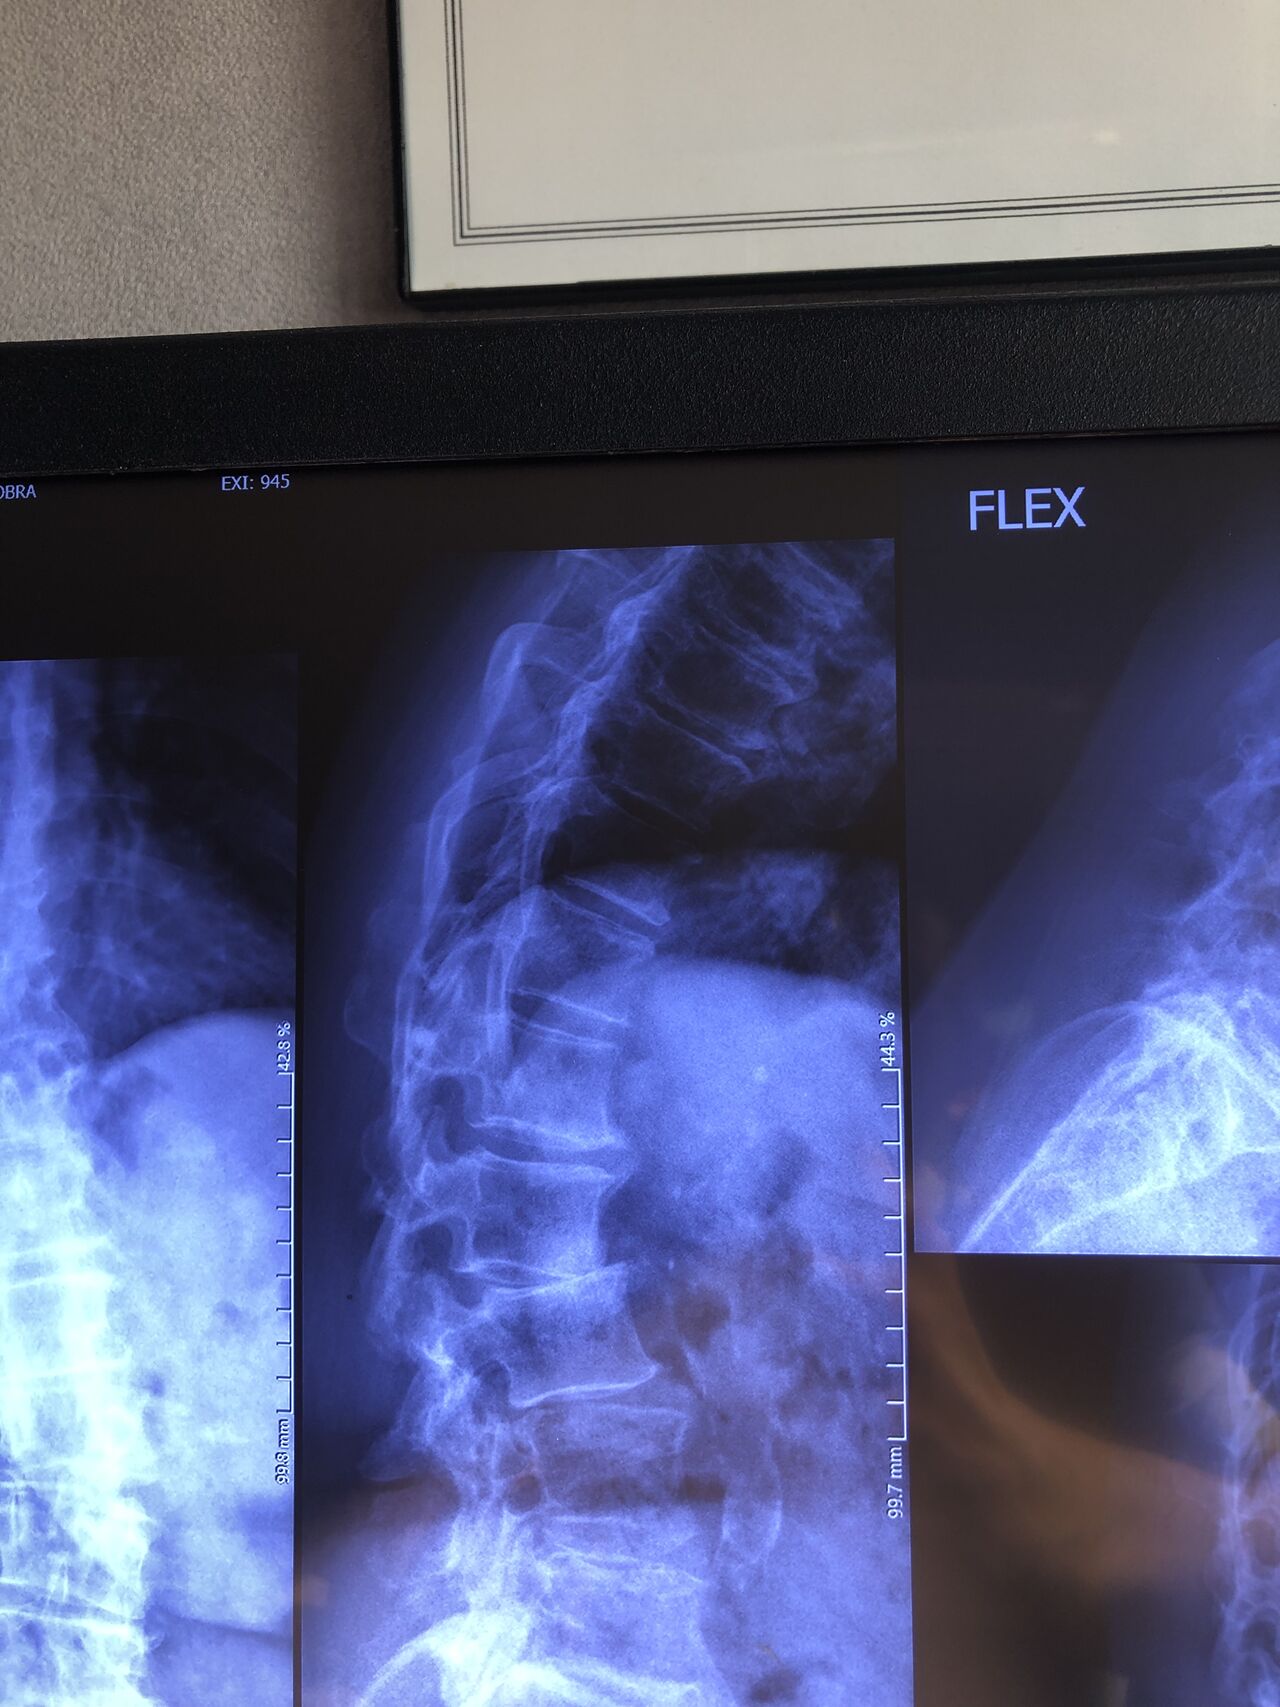

This time presented to my cl with LBP mainly during sleep at night. Just brought me her mri. According to her mri I ordered dynamic L/S X. R.

I didn’t accept her to give treatment. I referred her to her surgeon. What are your findings in her mri and X. Rays?

Is ant listhesis of L4 unstable or stable?

From several compression fractures we see which of is acute/ subacute and which ones are chronic fx?